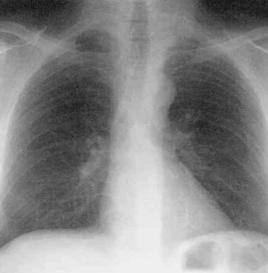

胸部X線檢查:早期可無異常,或僅見肺尖部模糊陰影,當腫塊逐漸增大時,可出現肺內凸出的塊狀陰影,1~3肋骨常被侵蝕糜爛,附近脊椎骨也可被破壞。

根據臨床表現、胸部X線檢查,初步可作出診斷。